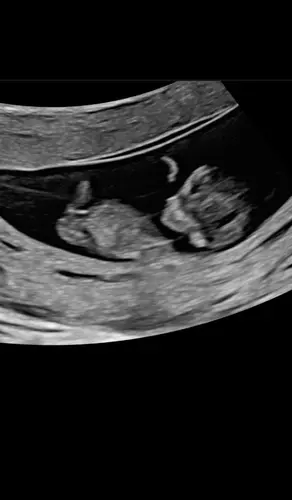

Mijn termijn echo 1-8-26

Hier blijft het 3-8, alles zat goed gelukkig. Op de foto niet te zien, in de echo armpjes en beentjes waren al aan het trappelen.

Paar dagen vooruit gezet, wordt 1-8. Allebei helemaal in orde en lekker druk 🥰

Van 4-8 naar 2-8 gezet. Wat was het leuk om te zien hoeveel het in korte tijd gegroeid is. Zelfs de voetjes en teentjes waren al goed te zien🥹.

Dit is die van vandaag kreeg 2 dagen later aan gegeven dan eerst nu 6-8 uitgerekend

Zo intens spannend, van de eerste echo met 7+2 moeten wachten tot vandaag 11+2. Maar het was het wachten waard en we hebben een super goede 2e echo gehad! ❤️ datum stond al vast ivm icsi 01-08-2026, groei loopt wel 2 dagen voor 🤗🥰

Vandaag een goede termijnecho gehad. Weer 2 dagen naar voren gezet dus nu 11w+2d. Uitgerekende datum staat vast op 2 augustus. 🩵🩷

Ons hummeltje wilde zich niet goed laten zien, dit was maar 1 seconden maar gelukkig gemeten en we zijn weer 5 dagen vooruit gezet. 30/7 uitgerekend ✨

Hier vandaag termijn echo gehad met 10+4, baby word 11 weken gemeten maar omdat ik iui gehad heb blijft de uitgerekende datum 7augustus🥰

Hier termijn echo gehad met 10 +6, alles zag er goed uit!

Termijn echo van 10 +4 ons kindje was 2 weken geleden 8+4 dus echt mooier kan niet! Mooie walnoot hersentjes gezien , er werd nog naar ons gezwaaid door ons kindje en ook het blaasje was al te zien. De verloskundige was onwijs tevreden! En wij ? Wij ZO trots

Hier ook alles goed! De kleine heeft gezwaaid en alles, heel erg leuk! Pak van mijn hart. Nu ga ik de rest van de avond naar dat zwaaitje kijken op repeat 🔁

Hier 9 weken en 1 dag 🥰 mooi kloppend hartje en armen en benen druk aan het bewegen